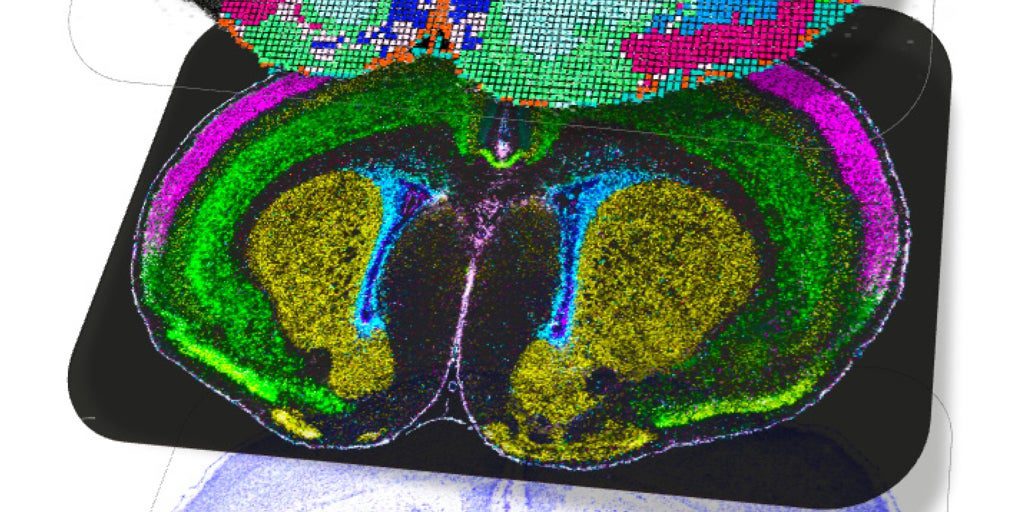

Del autismo al autismo y a la esquizofrenia. Información publicada en ‘Nature’ de 12 estudios del consorcio internacional BRAIN Initiative Cell Atlas Network (BICAN) sobre los mapas más detallados hasta la fecha del desarrollo cerebral en mamíferos, incluidos los ratones, … sino también en humanos, proporciona información detallada sobre cómo nacen y maduran los diferentes tipos de células cerebrales a lo largo del tiempo y, según los autores, estos datos permitirán empezar a descubrir cómo las alteraciones en este proceso pueden conducir a trastornos como el autismo o la esquizofrenia.

Los resultados revelan con una resolución sin precedentes cómo los diferentes tipos de emergen las células cerebrales y especializarse desde las primeras etapas de la vida, así como los factores genéticos y ambientales que influyen en estos procesos

Utilizando tecnologías de secuenciación unicelular y herramientas avanzadas de mapeo espacial, los investigadores pudieron seguir paso a paso cómo las células madre se transforman en neuronas y células gliales, y cómo éstas se organizan en redes funcionales.

Los atlas producidos por BICAN incluyen datos de más de 1,2 millones de células cerebrales y abarcan desde ratones hasta humanos. Estos recursos muestran que el desarrollo neuronal continúa incluso después del nacimiento, particularmente en las regiones involucradas en el aprendizaje, la toma de decisiones y las emociones, lo que sugiere que el cerebro conserva una plasticidad notable durante la infancia.